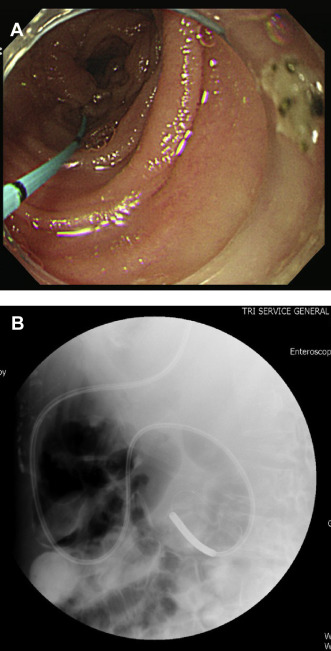

A 54-year-old woman had been diagnosed 6 months previously with retroperitoneal metastatic squamous cell carcinoma (cTxNxM1) without a definitive origin. She presented on this occasion with the symptoms and signs of intestinal obstruction. An upper gastrointestinal barium study showed external compression over the third to fourth portion of the duodenum and the gastroenterologists were consulted about the placement of an enteral tube.

The major obstacle to directly guiding the placement of the feeding tube by endoscopy was the location of the deeper obstruction, which was only accessible by single-balloon enteroscopy. To overcome this problem, we used the same technique as in Case 1; the procedure went smoothly and the tube was successfully placed into the jejunum (Fig. 2 A and B).

(A) A guide wire is placed into the jejunum. (B) A 12-Fr feeding tube is ...

Figure 2.

(A) A guide wire is placed into the jejunum. (B) A 12-Fr feeding tube is successfully placed into the jejunum.